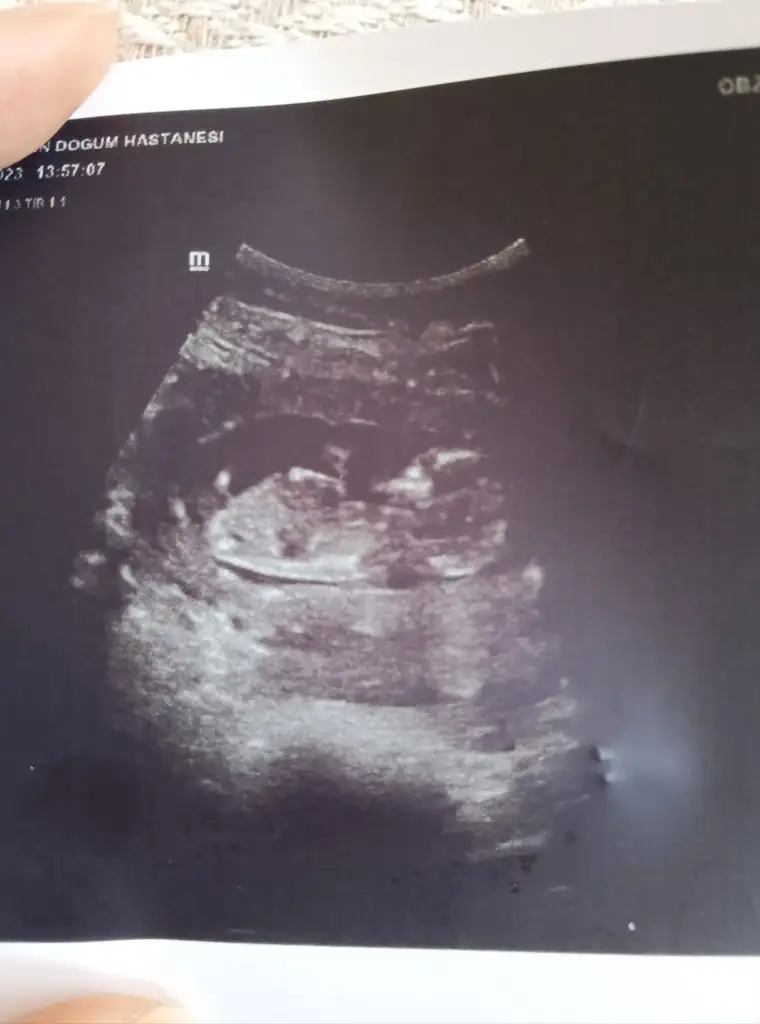

Kızlar merhaba bugün doktora gittim son adet tarihime göre 11+6 günlük gebeyim doktor ultrasonyonda 12+2 günlük dedi kilosu 50 gr boyu 6 cm doktor cinsiyet tahmini yaptı ama bize söylemedi kız kardeşime söyledi o süpriz yapıcak bize tahmin söyledi sadece 15.haftada kesin söylerim dedi sizce kız mı erkek mi? Birde ikili taramayı söyledi ama ben düşünmüyorum siz ne düşünüyorsunuz bu konuda ?